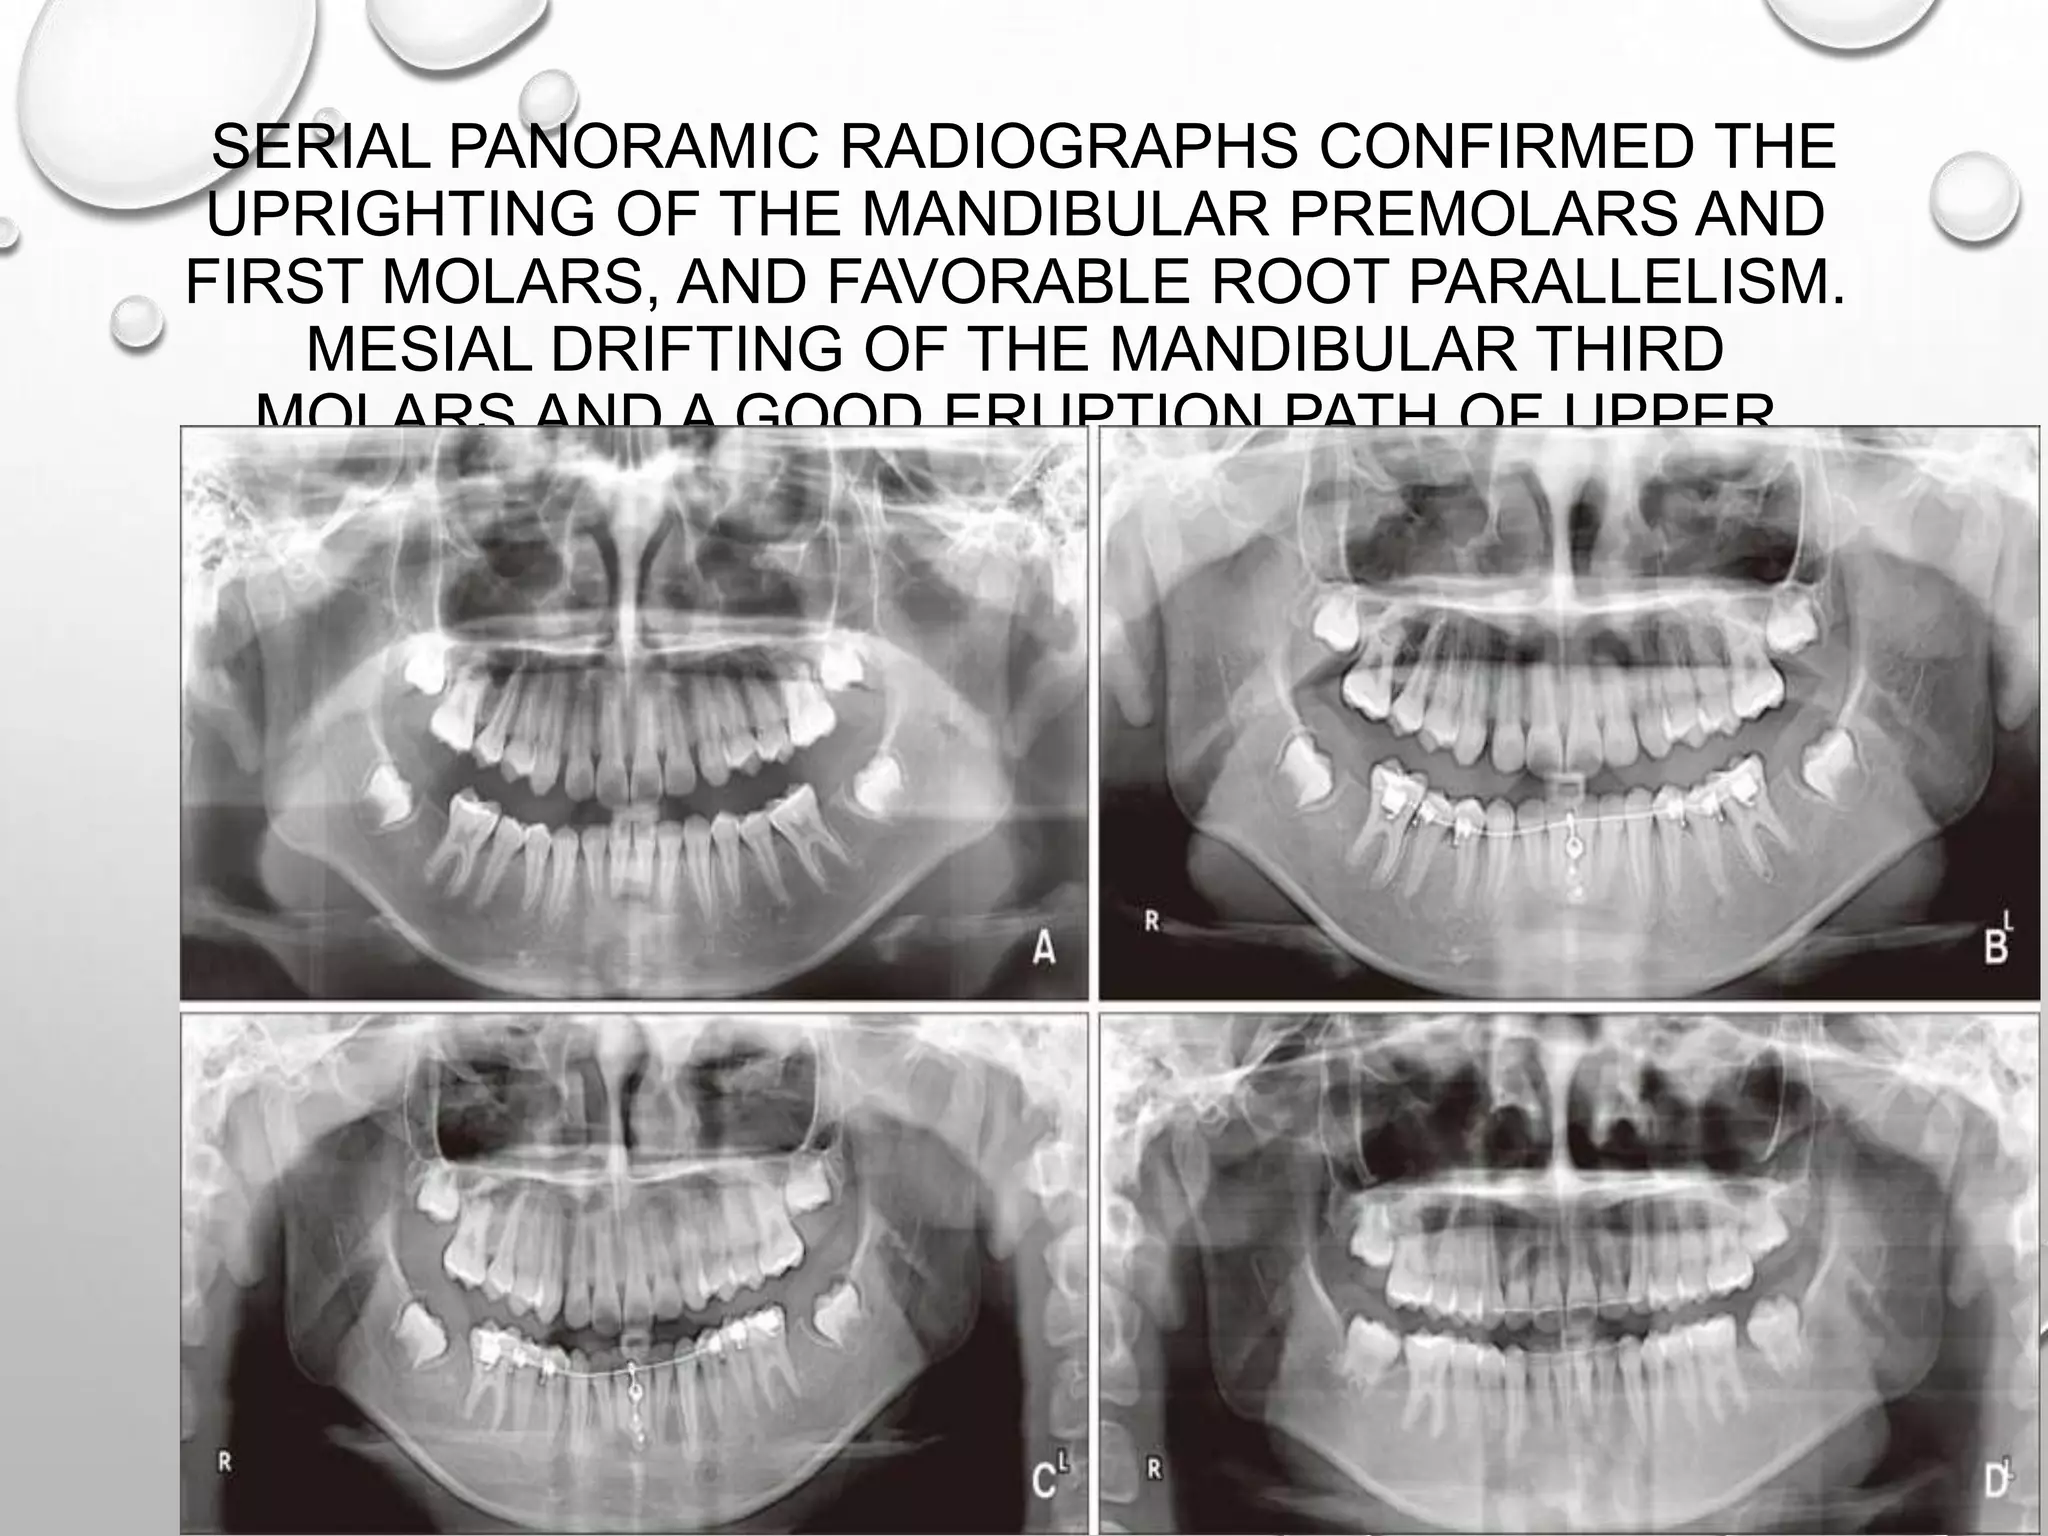

SERIAL PANORAMIC RADIOGRAPHS CONFIRMED THE

UPRIGHTING OF THE MANDIBULAR PREMOLARS AND

FIRST MOLARS, AND FAVORABLE ROOT PARALLELISM.

MESIAL DRIFTING OF THE MANDIBULAR THIRD

MOLARS AND A GOOD ERUPTION PATH OF UPPER

THIRD MOLARS